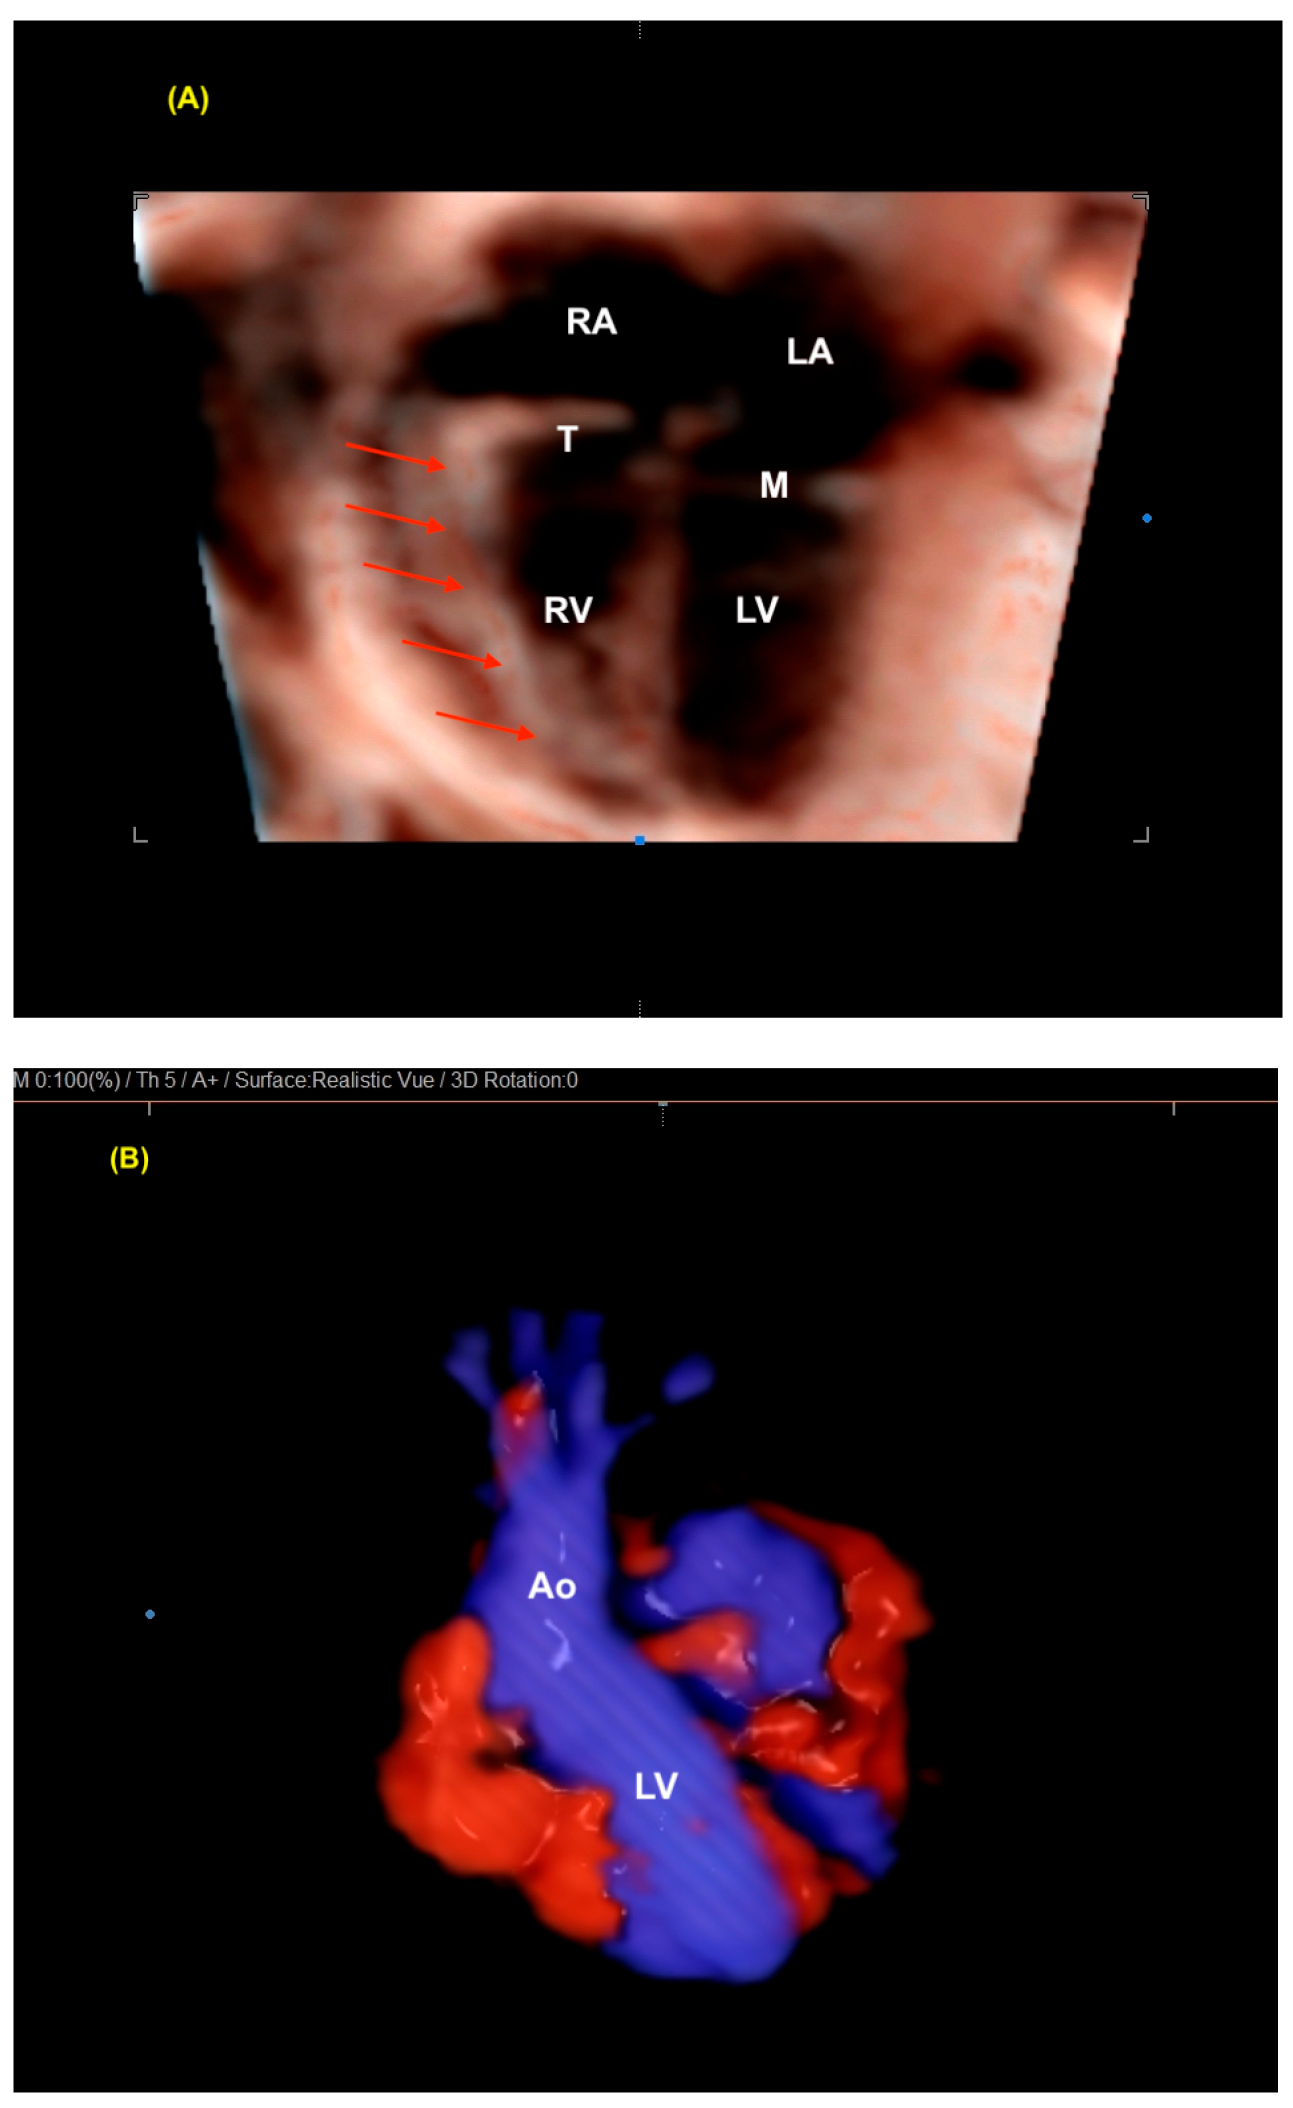

7. Isomerism

8. Atrioventricular Septal Defect

9. Tetralogy of Fallot